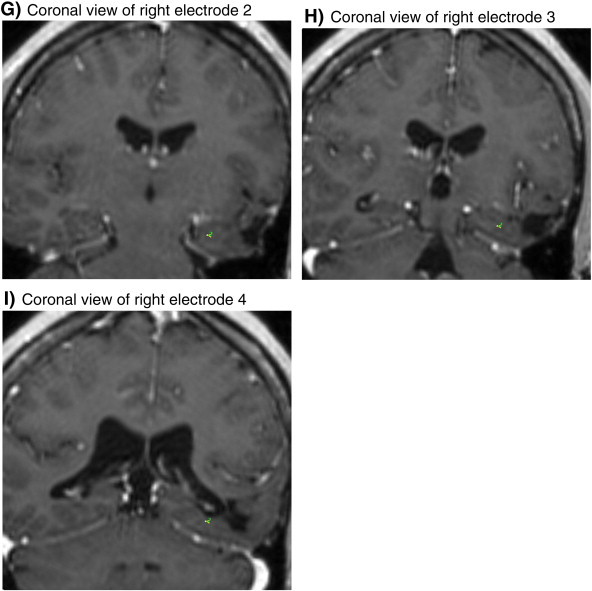

Fig. 1.

Image coregistration after device implantation. (A) The pulse generator is affixed within a ferrule in the skull and attached to the leads in the brain (not visible) by an insulated electrical conductor that is tunneled under the scalp. (B–I) Implanted electrodes in coronal view of coregistration where each aspect is orthogonal to the long axis of the hippocampus.

A track per DBS lead (NeuroPace, Mountain View, CA) targeted each anterior hippocampus using the microTargeting WayPoint Planner 2.0 software (FHC, Inc., Bowdoin, ME). Occipital lead entry points were chosen to avoid the ventricles, prominent veins, and arteries as visualized by the preoperative coregistered volumetric MRI and CT scans. On each side, a recording (Figs. 2A–E) was performed before implanting one four-electrode DBS lead, which was then connected to the pulse generator embedded in the right side of the skull (Fig. 1A).

The RNS™ device automatically stored four bipolar ECoG signals for each seizure: signals L1, L2, R1, and R2 respectively represented left electrodes 1–2, left electrodes 3–4, right electrodes 1–2, and right electrodes 3–4 (Figs. 1B–I). For each seizure, the RNS™ stored the four signals with corresponding date and timestamps (60 s before and 30 s after detection).